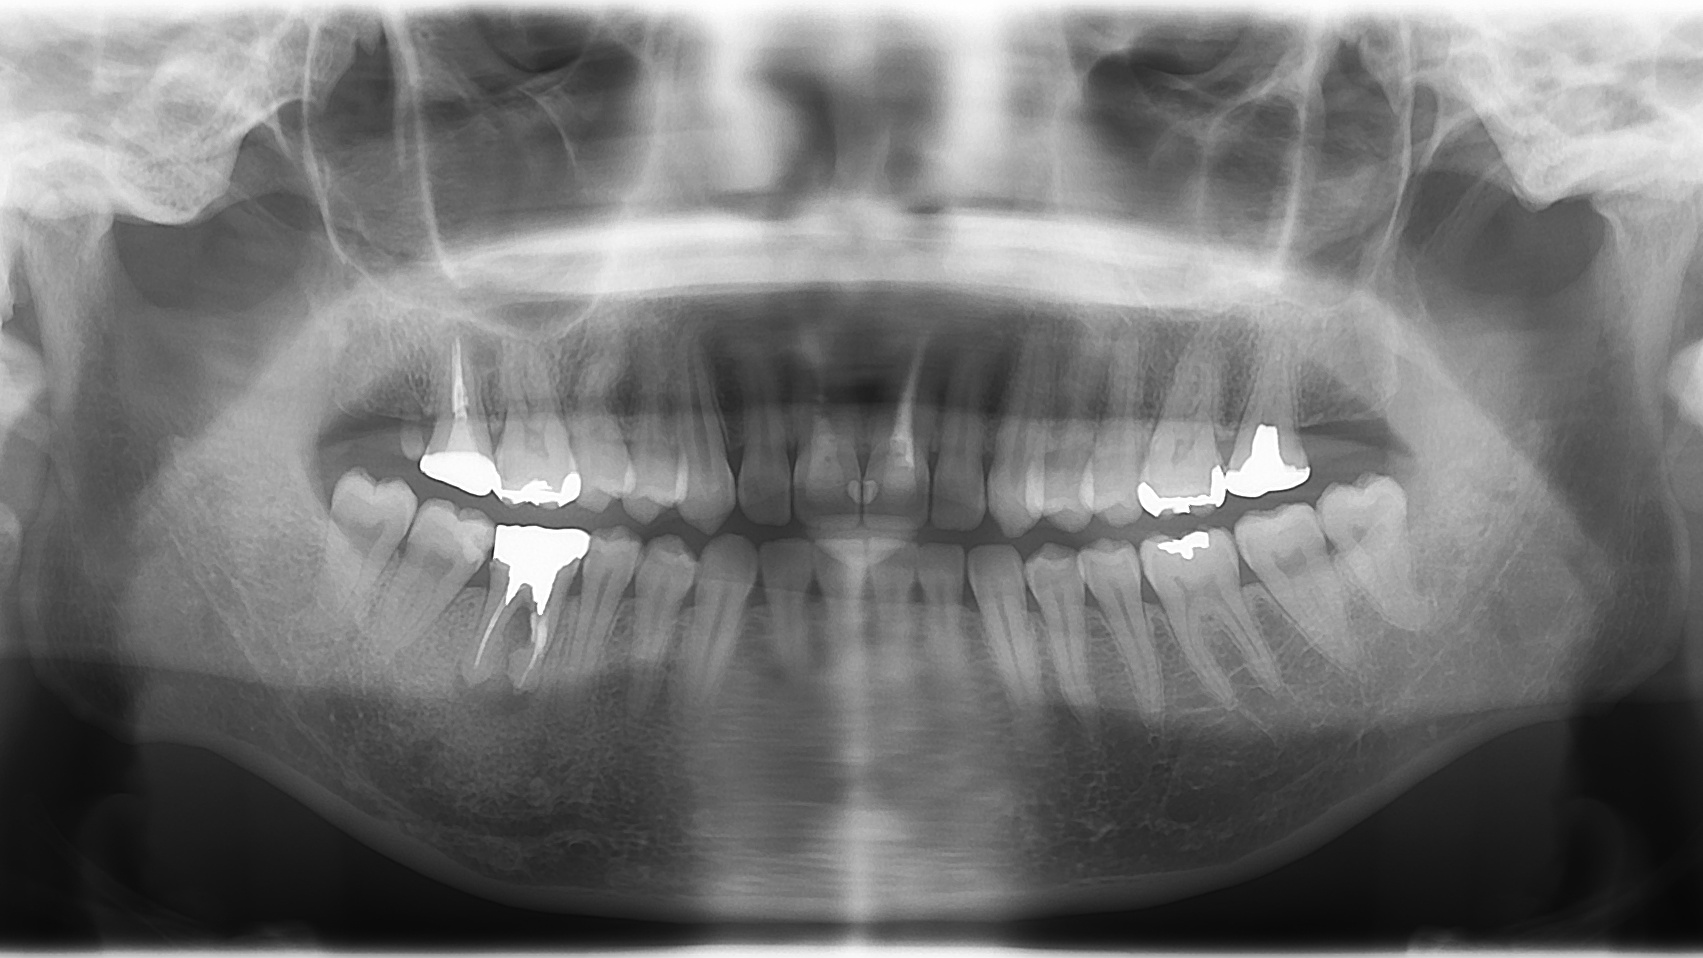

⑤ レントゲン写真の撮影

現状の歯と骨の状態を把握した上で、より的確な治療方針をたてるために当院ではレントゲン撮影を致します。お口の中の問題をより広く的確に調べるため、パノラマレントゲンというお口全体が写るレントゲン写真の撮影を勧めることもあります。デジタル化されておりますので被ばくも最低限で安心です。